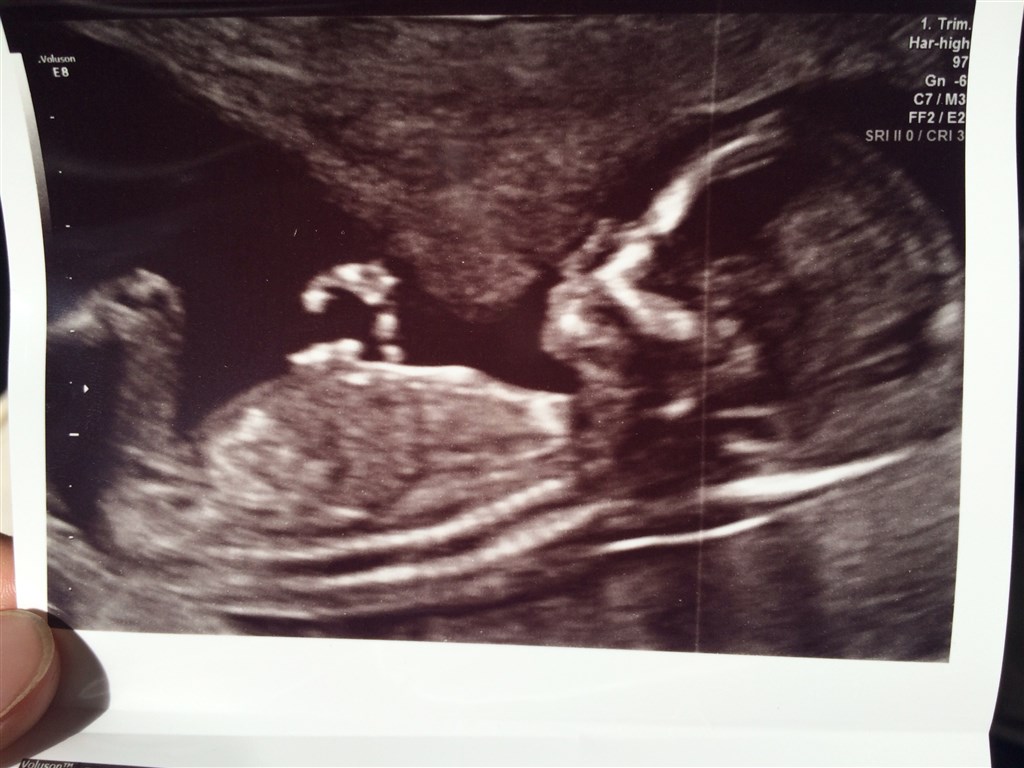

Vi var til nf idag og det hele så bare rigtig fint ud

Den lille var lige på grænsen til at være for stor til at lave udmålingerne

Men lykkes lige på et hængene hår

Blev scannet i 30 minutter da den lille fis blev ved med at vende ryggen til når der skulle måles

Fik fine tal og nogle dejlige billeder med hjem